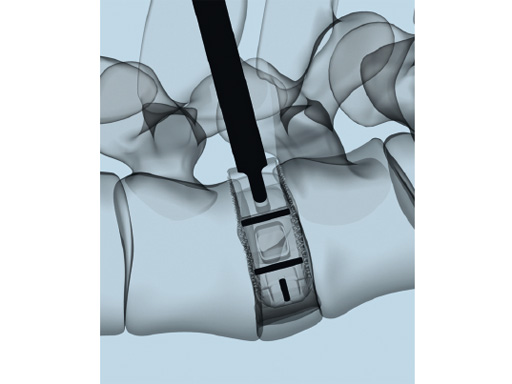

The key new feature of T-PAL is the guidance rails on upper and lower surfaces of both the trial and final implants which guide the implant into the final position. This self-guidance feature places the implant exactly where the surgeon desires it in the disc space and consequently saves time and eliminates the need to constantly readjust the insertion angle. Unlike traditional rigid trials, the T-PAL trial implant pivots, allowing it to be placed in the same location as the implant.

The kidney-shaped implants are manufactured globally from PEEK and most recently titanium (US only); they are available in two footprints (28 x 10 mm and 32 x 12 mm) and 11 heights (717 mm in 1 mm increments). With the exception of the shortest implant (7 mm high) all of these offer a 5 lordotic angle.